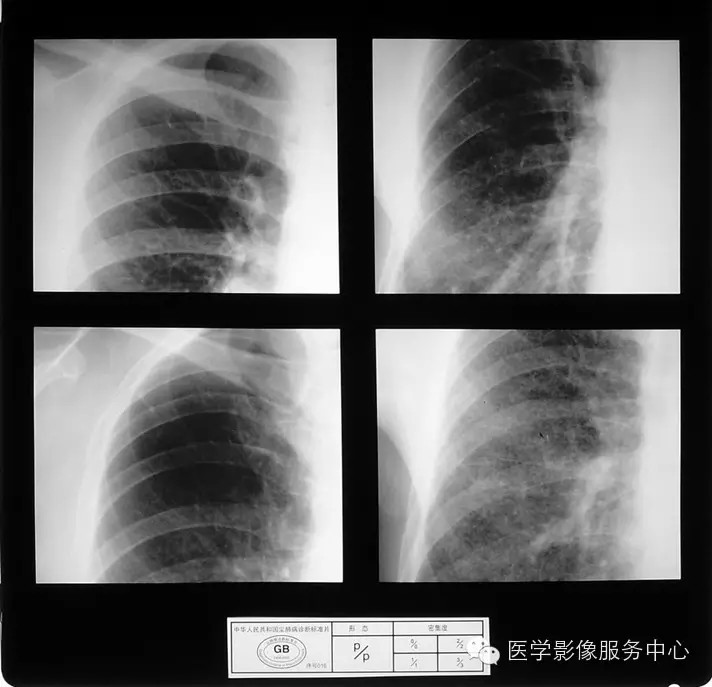

4.3 二期尘肺(Ⅱ)

a)Ⅱ:有总体密集度2级的小阴影,分布范围超过4个肺区;或有总体密集度3级的小阴影,分布范围达到四个肺区。

b)Ⅱ :有总体密集度3级的小阴影,分布范围超过4个肺区;或有小阴影聚集;或有大阴影,但尚不够诊断为Ⅲ者。